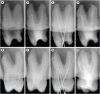

Objectives: This study aimed to investigate the efficacy of ionic and non-ionic-based contrast media (in vitro study) and the combinatorial effect of chitosan-based endo-radiopaque solution (CERS) (in vivo study) for visualization of the root canal anatomy.

Materials and methods: In vitro study (120 teeth): The root canal of maxillary premolars and molars (in vitro group 1 and 2 respectively, n = 60 each) were analyzed using 4 different contrast media (subgroups: Omnipaque 350, Iopamidol, Xenetix 350, and Urografin 76; n = 15 each) in combination with 5.25% sodium hypochlorite (NaOCl). Based on the results of the in vitro study, in vivo study (80 teeth) was done to compare Xenetix 350 + 5.25% NaOCl with CERS (in vivo group 1 and 2 respectively, n = 40 each) on maxillary and mandibular premolars and molars. Two endodontists used radiovisiography to assess the depth of ingress and identify the aberrant root anatomy after access cavity preparation, and after initial cleaning and shaping of canals. Kruskal-Wallis test was used for in vitro comparison (p < 0.05), and Wilcoxon signed-rank test and Mann-Whitney U test for in vivo analysis (p < 0.01).

Results: In vitro study, Xenetix 350 + 5.25% NaOCl facilitated a significant higher visualization (p < 0.05). For in vivo study, CERS had a statistically significant depth of ingress (p < 0.01), and was efficient in identifying the aberrant root canal anatomy of premolars and molars.

Conclusions: CERS facilitates better visualization of the root canal anatomy of human premolars and molars.